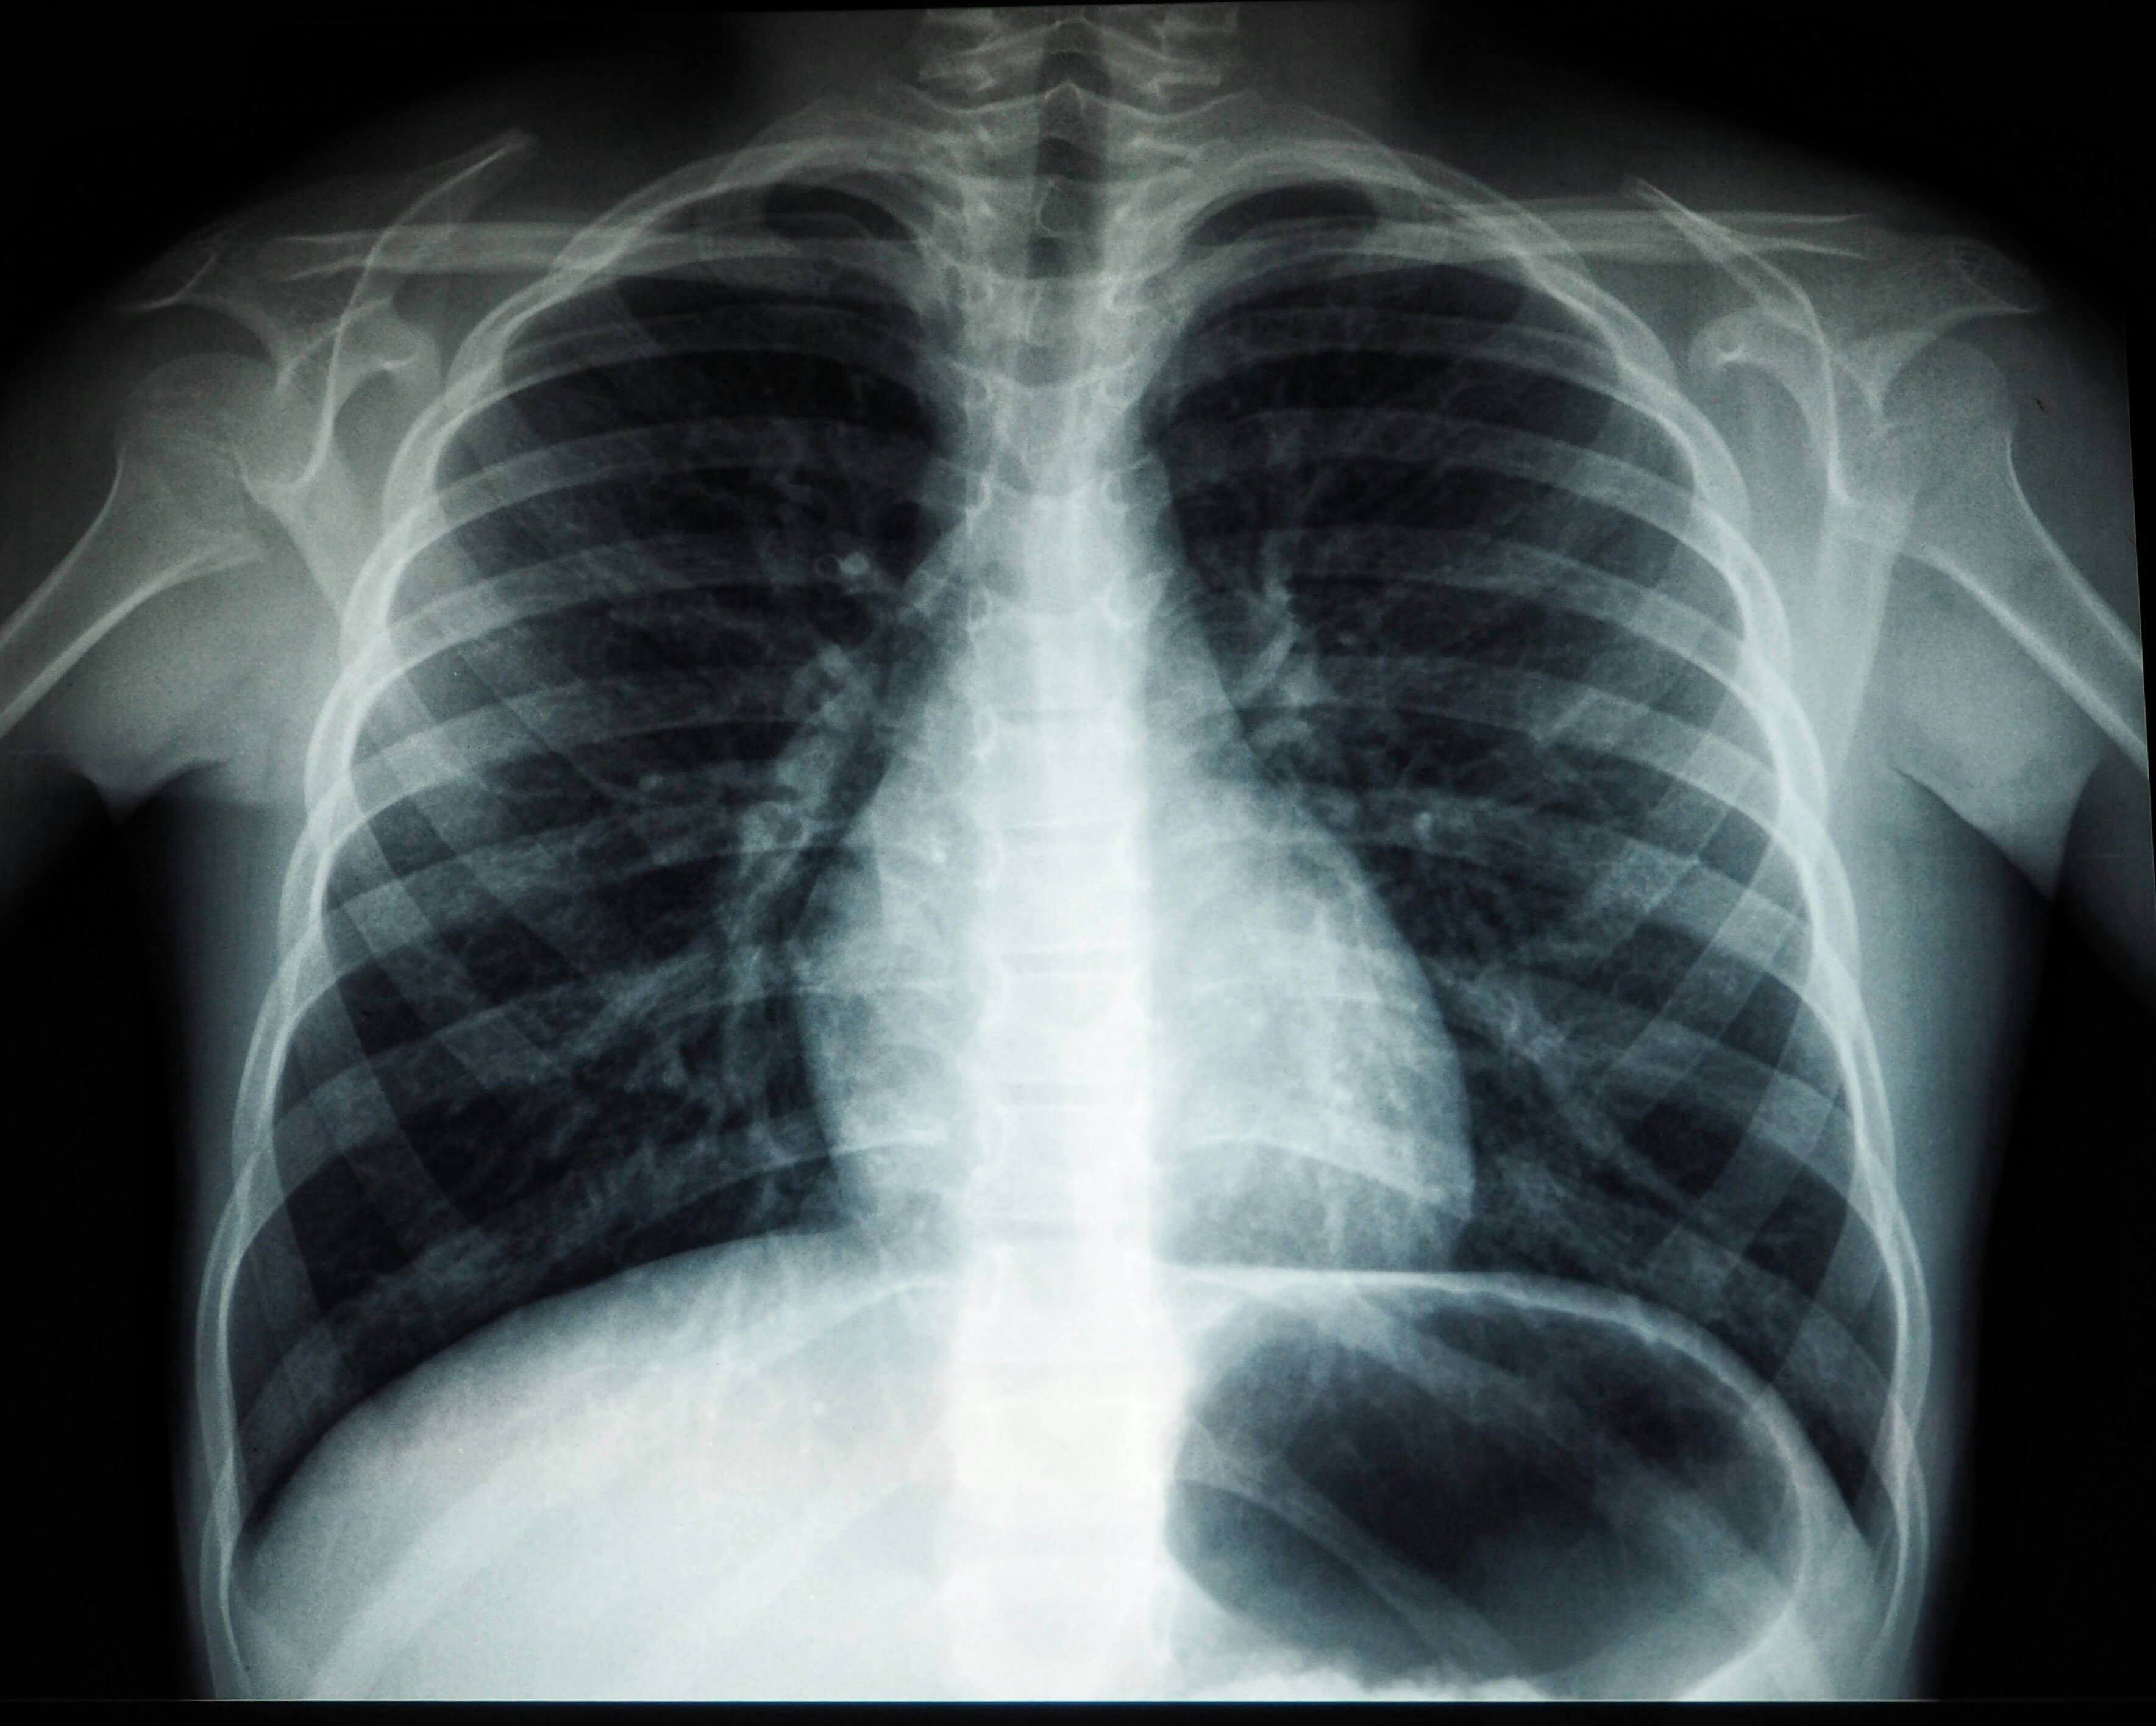

- 가슴 X선 촬영

- 가장 기본적인 진단 방법

- 폐 허탈 정도 확인

- 흉부 CT 촬영

- 수술 필요성 판단

- 기낭의 정확한 위치와 범위 파악

- 재발 위험도 평가